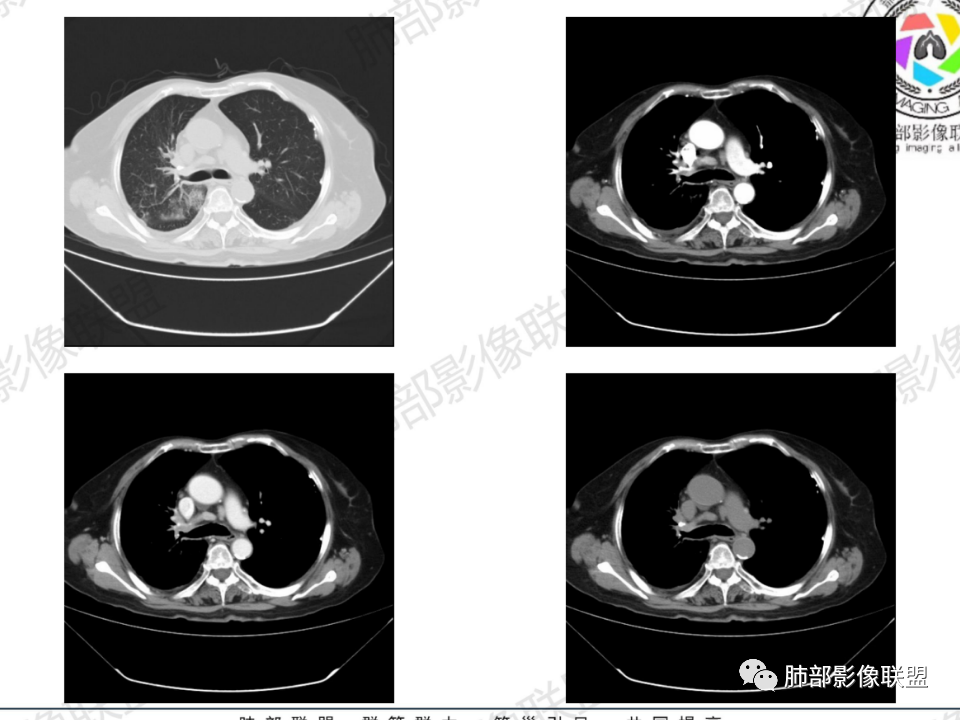

那个人:老年女性,亚急性病程,咳嗽发热。有垂体前叶功能减退,目前激素替代治疗,长期激素,量小,不知道累积量,没有目前激素水平指标。既往有淋巴结结核病史。肿瘤标记物Ca125升高。血沉升高,C反应蛋白轻度异常。影像,右肺上叶靠近肺门团块影,右肺门淋巴结钙化肿大,支气管狭窄,局部增厚,团块影外朝内改变,强化明显,血管破坏不明显,有粘液。和纵隔胸膜分界清楚,周围肺组织有斑片渗出影,右侧胸腔积液,考虑炎性?结核?支气管镜检查除外恶性飞鹰行动:老年患者,影像表现 右肺上叶占位性病变,边界清楚,有分叶征,内见细小钙化,右肺上叶支气管截断,增强病灶不均匀强化,病灶内有条状坏死区(扩张的支气管?),纵膈内未见增大淋巴结,考虑炎性病变,结核可能。一切∮随缘:右肺上叶实性肿块形态不规则,呈三角形,边缘分叶,边界伴有磨玻璃影,近段支气管未见明显显示,可能堵塞,病变平扫密度均匀,增强后可见低密度坏死无强化,周围略强化,右肺下叶散在结节。心包积液,及右侧胸腔积液,临床:有低热,低蛋白血症,肿瘤标记物高,考虑恶性:腺癌,神经内分泌癌(强化偏弱了),淋巴瘤,鉴别:结核红星:老年女性患者右肺上叶,肺门上区 分叶状肿块 ,右肺上叶支气管显示不清,增强扫描肿块,中等程度强化可见小斑片状坏死区,病灶内部可见斑点状钙化灶,病灶周围可见斑片状及小斑点状影,纵膈淋巴结增大,其他区域,胸膜下可见斑点状钙化。考虑肉芽肿性病变,结核的可能性大。老年患者最排除肿瘤性病变腺癌。土娃:右上肺不规则肿块影,边缘分叶,边界磨玻璃影欠清,病灶分叉状,内见点状钙化影及坏死灶,支气管堵塞,病灶增强强化不明显。考虑瘤样结核,鉴别淋巴瘤。张小兵:老年女性,亚急性病程,右肺上叶见不规则肿块,边缘平直凹陷为主,周围GGO边界不清,内见点状钙化及坏死灶,增强持续性渐进强化,右侧少量胸腔积液,双肺门及纵隔肿大淋巴结伴钙化,综合考虑慢性炎症。saf:老年患者,影像表现 右肺上叶占位性病变,边界清楚,有分叶征,增强病灶明显不均匀强化,纵膈内未见增大淋巴结,考虑炎性病变,结核可能。小兜:老年女性,咳嗽喘息一月,发热三天,肿瘤标志物升高,长期激素替代治疗。CT示右肺上叶近肺门不规则实变影,周围伴磨玻璃影,增强持续性渐进强化,内部血管破坏不厉害,内部可见多发条形低密度灶,右侧胸腔可见少量积液,双肺门及纵隔可见钙化淋巴结,考虑为炎性病变,结核可能玫:女,79咳嗽,喘息一月,发热三天入院,右肺上叶不规则形软组织密度肿块影,边界清晰,边缘见分叶及细短毛刺,病灶内见点状钙化影及稍低密度区,病灶边缘呈磨玻璃样改变,增强扫描,病灶呈不均匀性强化,考虑炎性病变,鉴别鳞癌。大雄:老年女性,既往诊断淋巴结结核,提示已治愈,近2年服用激素,诱导结核复燃→发热;纵隔肺门淋巴结肿大钙化,压迫支气管,右肺上中下叶支气管均狭窄→喘息咳嗽;尖段支气管受累闭塞→肺不张、支气管粘液栓;累及胸膜,结核性胸膜炎并胸水→右侧胸痛;实验室,血沉快,CA125高,低蛋白,符合;下一步,支气管镜尖段支气管刷检抗酸染色周太狼:老年女性,亚急性病程,肿瘤标志物升高。CT示右肺上叶尖段不规则肿块影,有分叶、收缩,周围伴磨玻璃影,增强渐进强化,内部可见多发条形低密度灶,右侧胸腔及心包少量积液,纵隔内淋巴结稍增大。倾向于恶性病变,肺癌伴阻塞性炎变可能。丽:老年女性,右肺上叶不规则软组织肿块,边缘清晰,内密度不均,可见点状钙化及粘液栓,周围可见片状高密度影,增强后均匀强化,内多发低密度,纵膈多发钙化淋巴结,考虑结核可能大,建议结合支气管镜检查除外肿瘤宇宙:右胸廓缩小,右肺上叶团块影及不张,平直边,周围磨玻璃影,纤细胸膜牵拉,上叶尖段支气管堵塞,明显延迟强化,可见支气管粘液栓,两肺门钙化淋巴结,右侧胸水,考性炎性肉芽肿,鉴别腺癌王秀仙:右肺上叶肺门区肿块,上叶支气管开口阻塞,形态不规则,密度不均,内可见支气管粘液栓及多发小灶性坏死,周围磨玻璃影边缘模糊,渐进强化,右侧胸腔积液、胸膜钙化,考虑炎性肉芽肿性病变,慢性炎症。鉴别鳞癌,结核。刘丹:老年女性,右肺上叶肿块伴钙化,右肺上叶支气管截断,增强后均匀强化,周边可见点片状模糊影,右侧胸腔积液,右肺门淋巴结增大,考虑占位并阻塞性炎症,肿瘤?结核?建议纤支镜检查。小飞:右肺上叶纵隔旁软组织肿块,边缘深分叶、长毛刺及毛刷样短毛刺,边缘磨玻璃影,磨玻璃边界模糊,支气管截断,平扫密度不均,可见点状钙化,增强不均匀明显强化,心影增大,心包积液,右侧胸腔积液,考虑恶性肿瘤,腺癌?秦化君:右肺上叶不规则分叶软组织密度肿块,边缘清晰,胸膜牵拉,周围花花草草,上叶尖段支气管阻塞,内可见点状钙化,增强后密度不均可见支气管粘液栓及坏死区,内见血管分枝。中间段及中叶,下叶支气管狭窄,壁见钙化。右肺门淋巴结肿大,右侧胸腔积液,心包粘连肥厚。考虑1右上肺恶性病变,鳞癌?2右肺多叶段支气管狭窄,考虑支气管内膜结核?3胸腔积液及肺门淋巴结肿大,转移?风儿:老年女性,右肺上叶肿块,形态不规则,外围大内带小,边缘分叶膨隆平直及毛糙,密度不均,内见支气管粘液栓及多发小灶性坏死,坏死边缘清晰 ,渐进强化,上叶尖段支气管阻塞,叶支气管壁有局限性增厚,邻近胸膜腔微积液;纵隔及双肺门淋巴结肿大,部分钙化,右侧胸腔积液、心包积液、胸膜钙化,考虑炎性,肉芽肿性结核可能性大。鉴别鳞癌,女性及血供均不支持;腺癌,坏死边界太清晰。流心明智:老年女性,79岁,咳嗽、气短1月,发热3天。胸CT:右肺上叶见不规则肿块,边缘有膨隆、有平直凹陷,周围GGO边界不清,病灶内见点状钙化、粘液栓,尖段支气管未见,增强持续性渐进强化,右侧少量胸腔积液,双肺门及纵隔肿大淋巴结伴钙化,肺动脉增粗。考虑:右上叶尖段堵塞并慢性炎症,支气管TB并结石?鉴别Ca

临床信息:老年女性,亚急性病程,咳嗽发热。有激素使用史。既往有淋巴结结核病史。肿瘤标记物Ca125升高。血沉升高,C反应蛋白轻度异常。 影像所见:右侧胸廓相对狭小,右肺上叶不规则团块影贴附纵隔旁,轻度分叶,整体密度较均匀,偶见钙点。

相应上叶尖端及前段支气管开口未能追踪(阻塞),开口处见钙化。病灶渐进性强化,并衬托出较完整尖段及前段含液支气管影。支气管开口区域未见异常高密度强化(如类癌等)及相对乏血供区(如鳞癌)。病灶区未见液化坏死。右上纵隔及胸廓入口区未见病灶胸膜外突破(栽赃)。

右肺上叶后段等区域散在片状影,边界不清(提示渗出性病灶)。

纵隔及双肺门见钙化淋巴结。心包积液,右侧胸腔积液(提示存在活动新病灶)。双侧胸膜下见多发斑点状钙化,胸廓变形(提示存在结核基础病变可能)。 诊断意见:综上,右肺上叶块状影更符合继发性肺结核。 最后小结:既往诊断淋巴结结核,提示已治愈。近2年服用激素,可疑诱导结核复燃,也可引起发热。纵隔肺门淋巴结肿大钙化,压迫支气管,右肺上中下叶支气管均狭窄,所以引起喘息咳嗽。尖段支气管受累闭塞,导致肺不张、支气管粘液栓,出现条状无强化区。病变累及胸膜,导致结核性胸膜炎并胸水,引起右侧胸痛。实验室检查血沉快,CA125高,低蛋白,均符合结核。下一步,建议支气管镜尖段支气管刷检并抗酸染色。(本段摘自於雄老师精彩发言)